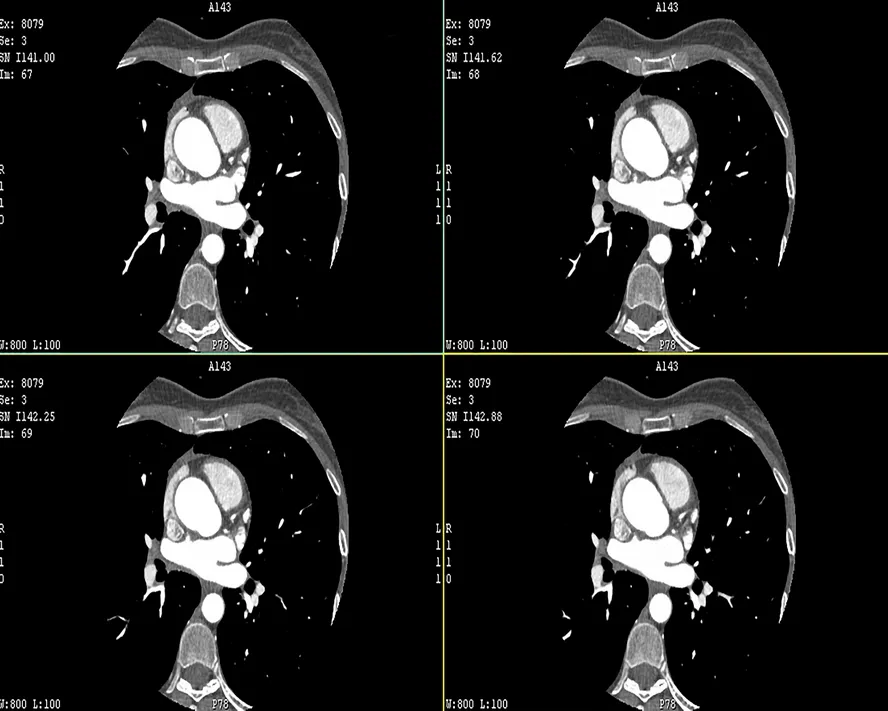

Koroner Arter Bypass Cerrahisi

Koroner Arter Bypass Cerrahisi Nedir?

Koroner arter bypass cerrahisi (CABG), kalbi besleyen koroner arterlerde meydana gelen daralmalar veya tıkanıklıklar nedeniyle kalp kasının yeterince oksijen alamadığı durumlarda uygulanan bir cerrahi tedavi yöntemidir. Bu cerrahi müdahale, tıkanmış veya daralmış olan koroner arterlerin etrafından kanın yeniden akmasını sağlamak için yeni bir yol oluşturmayı amaçlar.